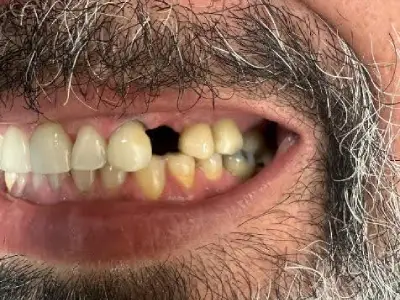

פליפר – תותבת חלקית זמנית

"פליפר" (תותבת חלקית זמנית נשלפת) הוא סוג של תח"ל קטן (תותבת חלקית להוצאה) המשמש בדרך כלל כשיקום זמני כדי לתת בעיקר מענה קוסמטי בקדמת הלסת, ועד לשיקום הקבוע.